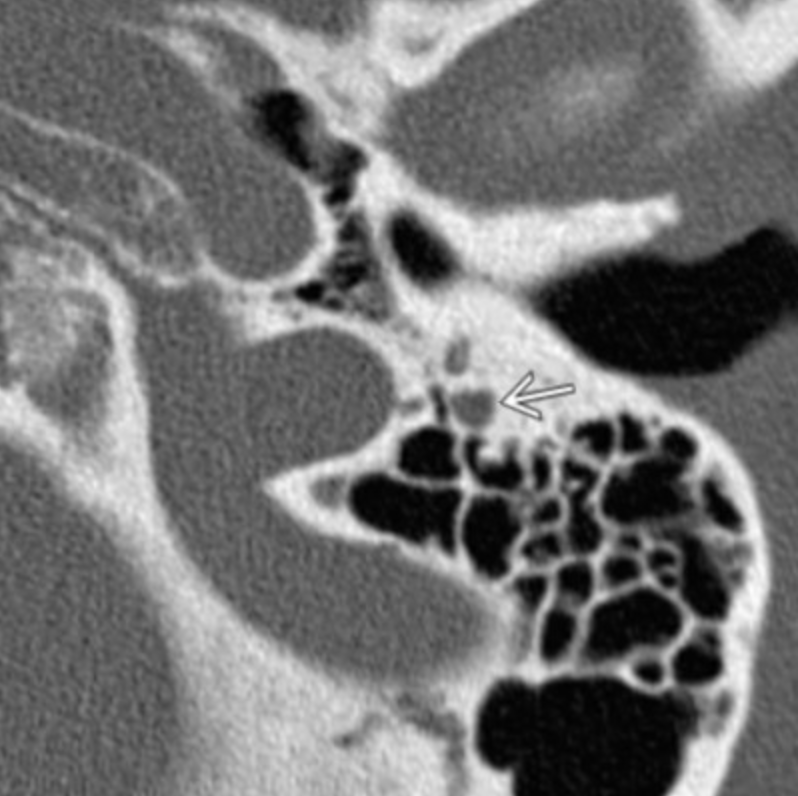

Sphenopalatine Foramen

• #1 in image to the right

• Allows passage of nasal cavity and pterygopalatine fossa

• Transmits

• Sphenopalatine artery & vein

• Nasopalatine nerve

• Posterior superior nasal nerves

• Clinical relevance

• Because nerves travel through here, it allows a possible passageway for peri-neural spread of malignancy from the nasal cavity to deeper structures

• Juvenile Angiofibromas